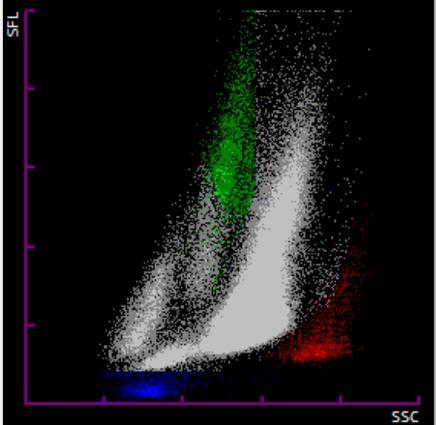

En la Figura 3a podemos observar los scattergramas de un paciente en los que se observa una población de eritrocitos nucleados de 3,6 células por cada 100 leucocitos con una hemoglobina normal (14,1 g/dL; VR: 13,5-17,2) con microcitosis (VCM 71,3 fL; VR: 80-100). Al realizar el frotis de sangre periférica (Figura 3b) se confirmó la presencia de eritroblastos y se observó una serie roja con distribución anormal de la hemoglobina y presencia de abundantes dianocitos. Se descubrió así mismo un cristal de hemoglobina C (marcado en rojo). Tras la realización de un estudio de cadenas de hemoglobina por HPLC, se descubrió una hemoglobina C homocigota y se derivó al paciente a consultas externas de hematología.

Figura 3. a) Scattergramas de un paciente donde se observa una población anormal de eritroblastos marcada en rojo. b) Frotis de Sangre periférica donde se observan eritroblastos (izquierda) y un cristal de hemoglobina C (derecha). Adaptado de: Calvo F, 2019